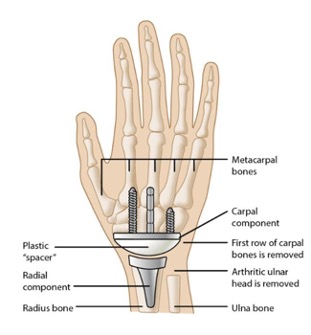

- The surgeon opens the back of the wrist with a precise cut.

- The surgeon eliminates the arthritic edges of the lower arm bones and may even remove the first row of carpal bones.

- The surgeon then places the prosthesis’ radial part within the center of the radius bone on the lower arm’s thumb side. This section will generally be secured with specialized adhesive cement.

- Based on the component design, a surgeon can place the carpal component into either the center hand bone (third metacarpal) or affix it to other rows of carpal bones with screws. Bone cement may guarantee stability; some carpals could be linked or fused.

- The surgeon precisely places a spacer of the correct size between the metallic components.

- After the procedure, the skin is meticulously sutured to close it. A splint may be added for extra support to ensure proper healing.